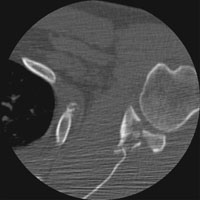

- Click on the image for a larger versionAAxial CT. This image through the glenoid shows a comminuted intraarticular fracture.

- Click on the image for a larger versionBAxial CT. This also shows the comminuted intraarticular fracture of the glenoid.